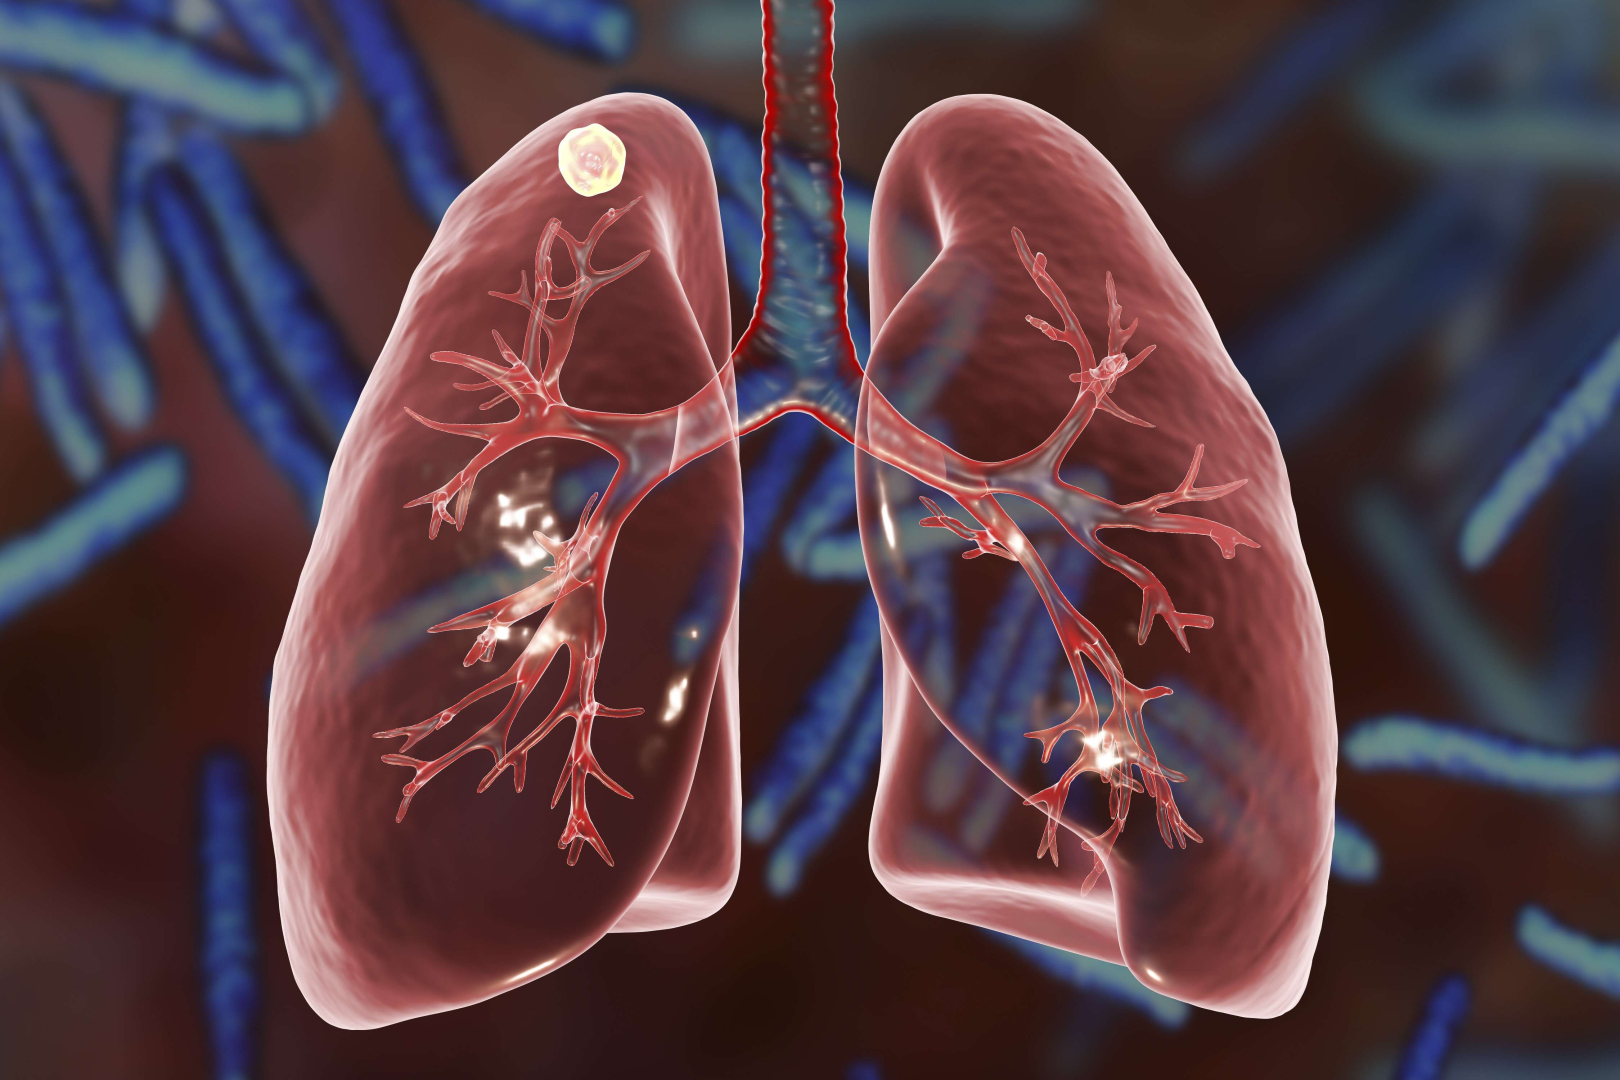

Tüberkülozun da Kovid gibi hava yoluyla bulaşan bir hastalık olduğunu belirten Prof. Dr. Özlü, "Gizli verem dediğimiz aslında bir hastalık değil. Sağlıklı kişi bunlar. Yani zamanında verem mikrobunu almış, vereme neden olan basil (bakteri) vücuda yerleşmiş, belli odaklarda canlılığını sürdürebilen ama hastalık yapmayan, bir belirtiye neden olmayan, dolayısıyla hasta olmadığı için tedavi de edilmeyen kişilerden bahsediyoruz." diye konuştu.

Özlü, "Gizli verem dediğimiz aslında bir hastalık değil. Sağlıklı kişi bunlar. Yani zamanında verem mikrobunu almış, vereme neden olan basil (bakteri) vücuda yerleşmiş, belli odaklarda canlılığını sürdürebilen ama hastalık yapmayan, bir belirtiye neden olmayan, dolayısıyla hasta olmadığı için tedavi de edilmeyen kişilerden bahsediyoruz. Bu kişiler taşıyıcıyken hastalığı bulaştırma şansları da yok. Taşıyıcıların yüzde 95-97'si bu süreci hiç hastalanmadan geçiriyor. Ama içlerinde bazıları enfeksiyonun seyri sırasında aktif verem hastası haline geliyor. Bunlarda daha çok, vücudun bağışıklık sistemini baskılayan durumlar söz konusu oluyor. İşte bu grup bizim için önemli." dedi.

"BURADA ASIL OLAN ŞEY, RİSK GRUPLARININ TEDAVİ EDİLMESİ" Prof. Dr. Özlü, "Bunlar da cilt testleri ya da bazı kan testleri. Bunu yaptığımızda o kişinin daha önce verem mikrobu ile karşılaşmış ve enfeksiyon sürecini geçirmiş olduğunu anlıyoruz. Her gizli verem tanısı konan hastaya tedavi gerekmiyor. Ama ileride aktif hastalığa dönüşme riski fazla olan kişilerin ‘koruyucu’ dediğimiz tedavileri alması önemli. Dünyada yaklaşık 2 milyara yakın insanın gizli verem vakası olduğu düşünülüyor. Türkiye'de ise nüfusun yüzde 10 ila 30’unda bu mikrobu taşıyan kişi var. Burada asıl olan şey, risk gruplarının tedavi edilmesi. Bu şekilde hem o kişileri korumuş oluyoruz hem de o kişiler hastalanırsa, topluma bulaştırmasını engellemiş oluyoruz" diye konuştu.